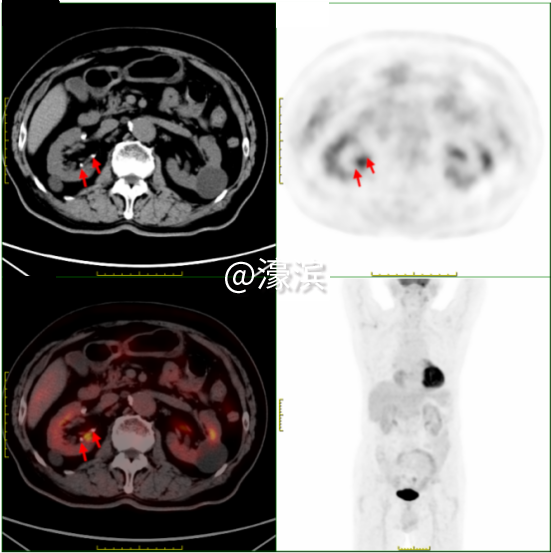

·0.2cm肝钙化灶(小于普通CT最小分辨单位)  ·0.6cm肾结石(超声检查受肠气干扰易遗漏) 精准诊断:全身隐匿病灶"无处遁形"

①食管癌精准定位 发现食管下段1.3cm管壁增厚伴FDG代谢增高(SUVmax 3.1),与病理结果高度吻合,为后续手术或放疗提供精准靶区定位。 ②全身隐匿病灶"无处遁形" 鉴别颈部炎性淋巴结(SUVmax 4.2)与转移灶,避免过度治疗;发现双肾囊肿(最大3.6cm)、肝囊肿等良性病变,完善全身健康评估;识别牙槽根周炎症(SUVmax 10.9)、上颌窦炎等感染灶,指导抗炎治疗。 ③全身健康"全景扫描" 同步检出肺气肿、冠脉钙化、前列腺增生伴钙化等退行性病变,精准锁定多处微小病灶,为多学科诊疗提供完整数据支持。 "对于SUVmax<2.5的病灶,如本例患者的食管癌灶,我们也能通过双能谱CT物质分离技术,识别早期癌变的特征性脂质成分变化。"瑞慈医院医学影像科核医学组主任夏淦林提到,"PET-CT不是简单的影像设备,而是现代精准医疗的决策中枢,精准捕捉到<1cm的微小病灶。" 选择瑞慈PET-CT的四大理由?  (一)美国GE进口超高清设备:高灵敏度、高清晰度、高分辨率、高扫描速度、高精准定量测量 (二)专业影像科团队:从业20余年的“南通PET-CT第一人”领衔解读诊断报告 (三)检查快速高效:提前一天预约即可检查,检查后最早当天下午出报告,最晚第二天上午出报告。 (四)星级检查环境:独立贵宾休息室,隐私零干扰、全流程单向通行,动线设计更科学。 PET-CT主要解决哪些问题? PET-CT在肿瘤方面的应用占其床应用的90%以上。 主要适应症如下: 协助诊断 ·对肿瘤高危人群,早期发现或排除肿瘤; ·对肿瘤标志物高或副肿瘤综合征患者,寻找肿瘤病灶所在; ·对已发现可疑病变者,鉴别良、恶性; ·对可疑肿痛患者,指导选择活检部位; ·对已发现肿瘤转移者,寻找原发灶。 指导治疗 ·对恶性肿瘤患者,进行更准确分期,全面了解全身病变情况; ·肿瘤恶性程度分级和预后判断; ·指导放疗计划靶区的设定。 疗效评估和复发监测 ·肿瘤治疗效果的评估; ·肿瘤残存病灶与坏死、纤维化组织的鉴别; ·肿瘤治疗后标志物仍高或重新升高,寻找残存、复发或转移病灶; ·肿瘤复发的监测。